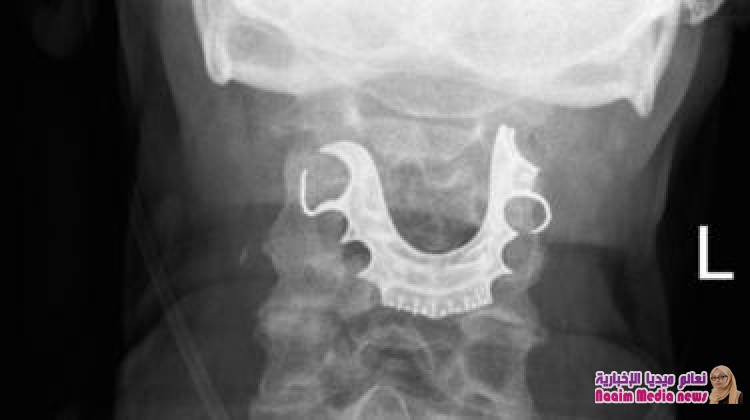

ولكن لما عاد الرجل إلى المستشفى بعد يومين، فحص فريق الأطباء حلقه وحنجرته ليجدوا شيئا شبه دائري يقبع على أحباله الصوتية.

ثم لم يلبث أن أخبر الأطباء عن فقدانه طقم أسنانه أثناء إقامته في المستشفى وخضوعه للجراحة.